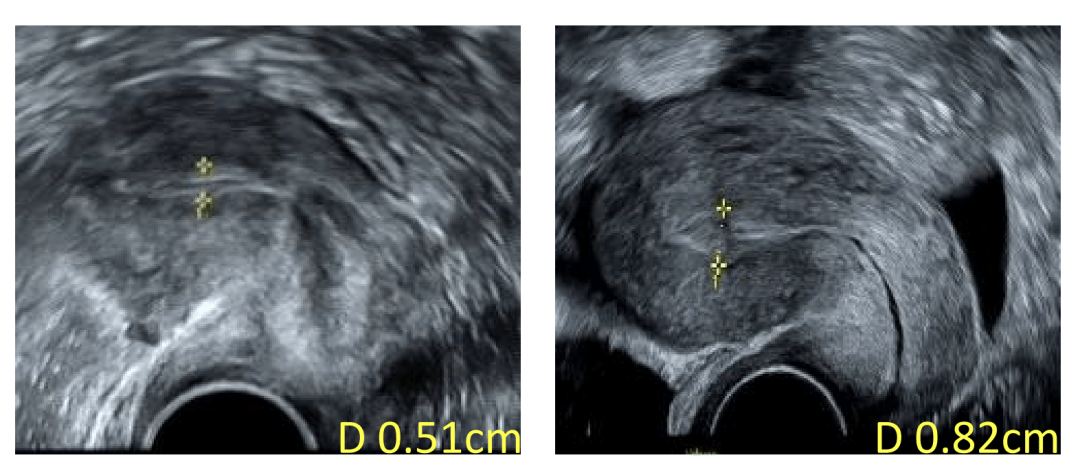

治疗后,王女士子宫内膜厚度得到明显改善,术后第二个月内膜厚度即超过8毫米。

治疗后,子宫内膜厚度(右)较治疗前(左)明显改善